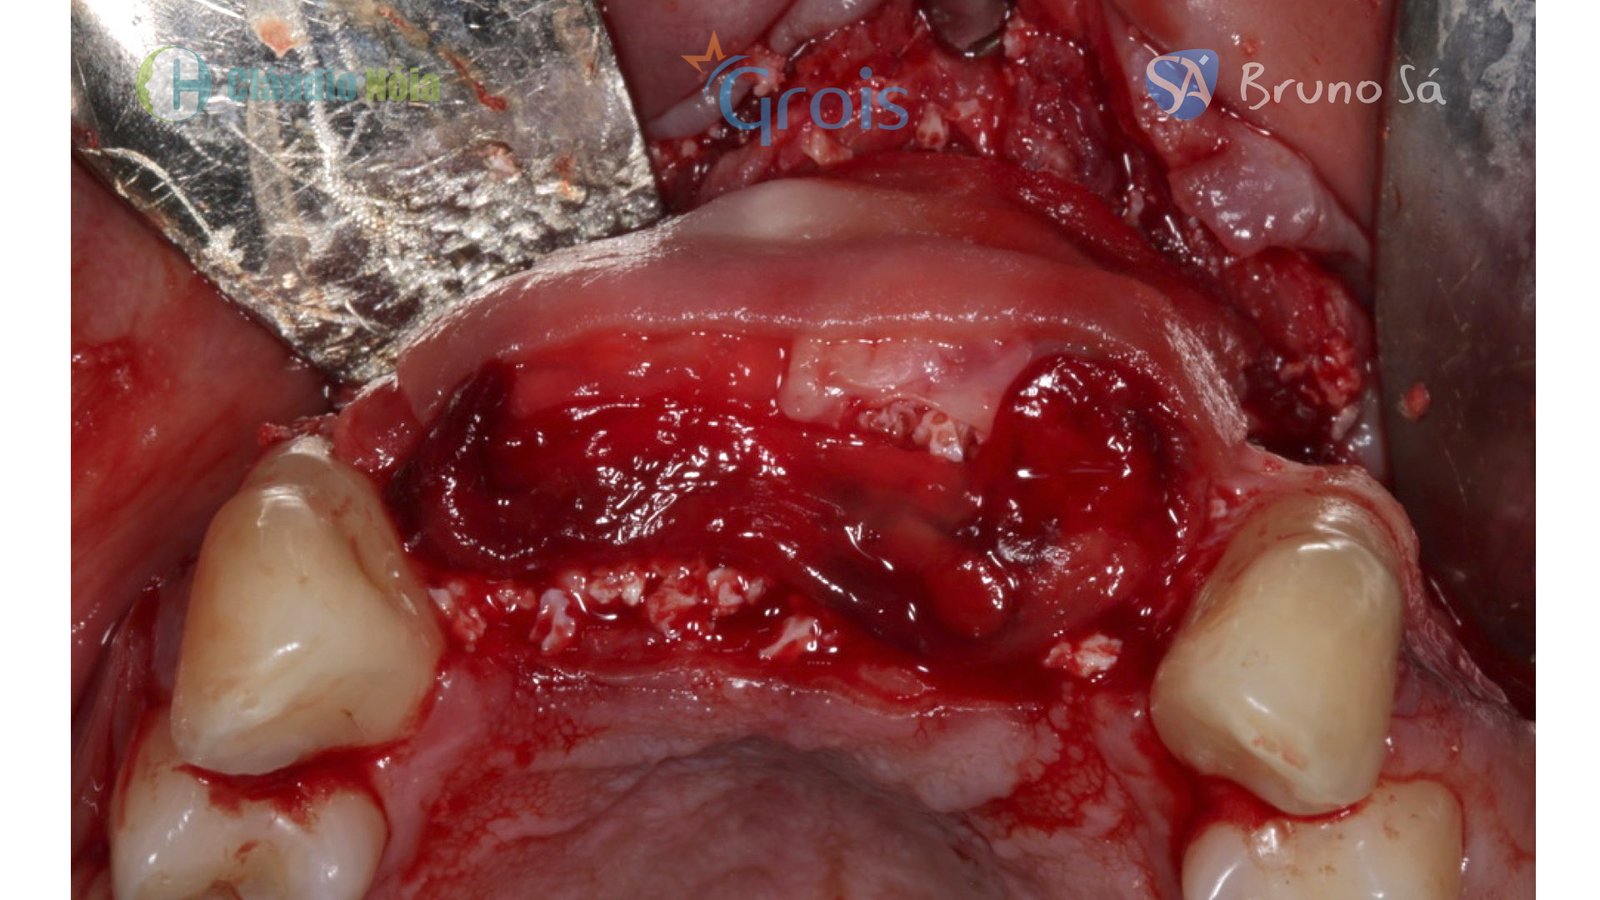

Paciente apresentou-se a Área de CBMF da Instituição com a pré-maxila edêntula (Figuras 1, 2 e 3) e foi submetido a técnica Screw Tent Pole utilizando os parafusos da linha Orth – Implacil de Bortolli (Figura 3). Do lado direito da pré-maxila foram instalados 3 parafusos que apresentavam roscas em toda superfície, enquanto que do lado esquerdo foram instalados 3 parafusos que não apresentam roscas no terço cervical (Figuras 4, 5, 6, 7 e 8). Biomaterial associado com PRF (Stick Bone) foi adequadamente acomodado na região e recoberto por membranas de PRF (Figuras 9, 10 e 11). Uma sutura livre de tensão foi realizada para finalizar o procedimento cirúrgico (Figuras 12 e 13).